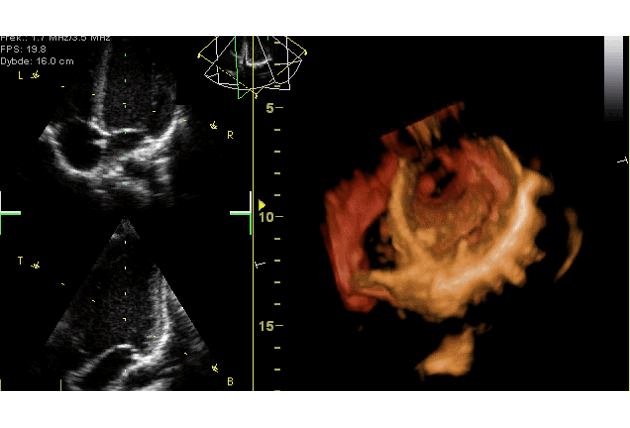

В основном для искусственного клапана сердца используются ксеногенные протезы. Они состоят из ткани крупных животных — быка, свиньи или лошади. Однако для любого протеза требуется особое покрытие. Оно должно иметь хорошую биосовместимость, минимальную токсичность, а главное — антимикробные свойства. Это особенно важно в первые дни после операции по установке протеза, когда организм уязвим к заболеваниям.

Так исследователи получили композит наноалмаз-лизоцим-мирамистин. Он покрывает коллагеновую матрицу сердечного клапана, равномерно затрагивая ворсистую и гладкую стороны. Ученые использовали матрицу с новым покрытием, чтобы определить его антибактериальную активность по отношению к золотистому стафилококку, который особенно активен после операции на сердце. Эти испытания провели специалисты из Национального медицинского исследовательского центра сердечно-сосудистой хирургии им. А.Н. Бакулева.